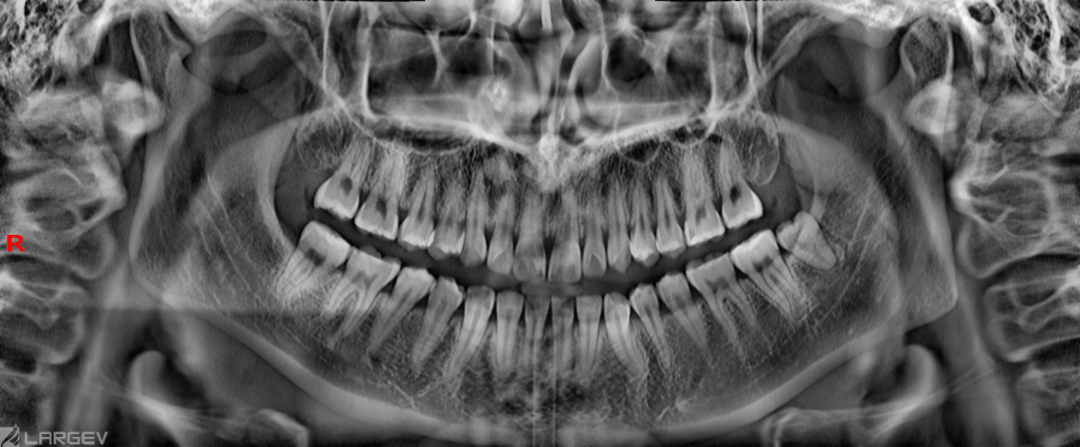

​ 全景摄影

内置多种曲面断层轨迹,贴合患者牙弓形态

软件内置多种曲面断层轨迹,可根据不同的患者牙弓形态进行切换。

全景智能自动聚焦技术,通过获取多张全景图像,并自动识别每张图像中最清晰的部位,拟合出与患者牙列最匹配的牙弓线形态,重建出的全景图像完美聚焦于每一颗牙齿,可以有效解决因摆位不准确导致的图像模糊问题,极大降低摆位难度,轻松获得优秀图像质量。